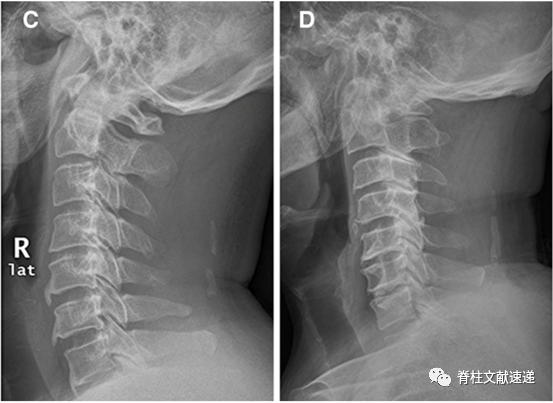

2.将项韧带骨化分成5型,如下图所示,分别为局灶型(A)、连续型(B)、间断型(C)、混合型(D)、其他型(E);

3.局灶型和连续型提示颈椎不稳,间断型、混合型和其他型提示OPLL的可能;

4.局灶型是最常见的项韧带骨化类型;

5.C4/5和C5/6是最常发生的节段。